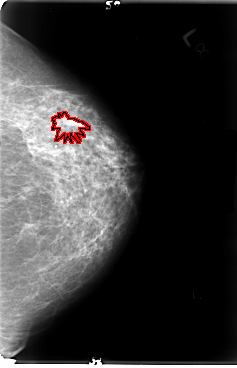

B_3042_1.RIGHT_CC

B_3042_1.LEFT_CC

LEFT_CC LINES 4776 PIXELS_PER_LINE 3080 BITS_PER_PIXEL 12 RESOLUTION 50 OVERLAY

FILE: B_3042_1.LEFT_CC.OVERLAY

TOTAL_ABNORMALITIES 1

ABNORMALITY 1

LESION_TYPE MASS SHAPE IRREGULAR MARGINS OBSCURED-ILL_DEFINED-SPICULATED

ASSESSMENT 4

SUBTLETY 3

PATHOLOGY MALIGNANT

TOTAL_OUTLINES 1

BOUNDARY